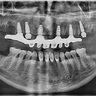

Делал имплантацию All-on-6 у Александра Игоревича в Stomarus. Консультация была понятной, все объяснили простым языком. ...Операция прошла спокойно, под хорошим обезболиванием. Команда внимательная, поддерживали на каждом этапе. Восстановление шло по плану, и теперь я наконец могу нормально жевать и улыбаться. Очень доволен результатом!

Делал имплантацию под наркозом. 3 часа работы врачей. Очнулся - зубов нет, ничего не болит, обезболивающее там и не пона...добилось. Через неделю поставили временный протез. Никакого дискомфорта. Спасибо хирургу Воробьеву Александру Игоревичу и особенно ортопеду Молчанову Виктору Александровичу и их помощникам. Да и сама атмосфера в клинике отличная.

В течение 5,5 месяцев посещала клинику (лечение, имплантация straumann, тотальное протезирование, установка виниров e. m...ax) и результат - ШИК! Слова благодарности хочу высказать Алейниковой Е., Воробьёву А., Молчанову В. Работа профессионалов в команде, внимательный подход оставил наилучшие впечатления. Девушки на ресепшене также внимательные. Советую всем знакомым именно эту клинику. После завершения комплексной работы на профосмотре была через 3 дня, месяц, запланировано через 3 месяца и полгода. Супер! Всегда получаю ответы на все вопросы.